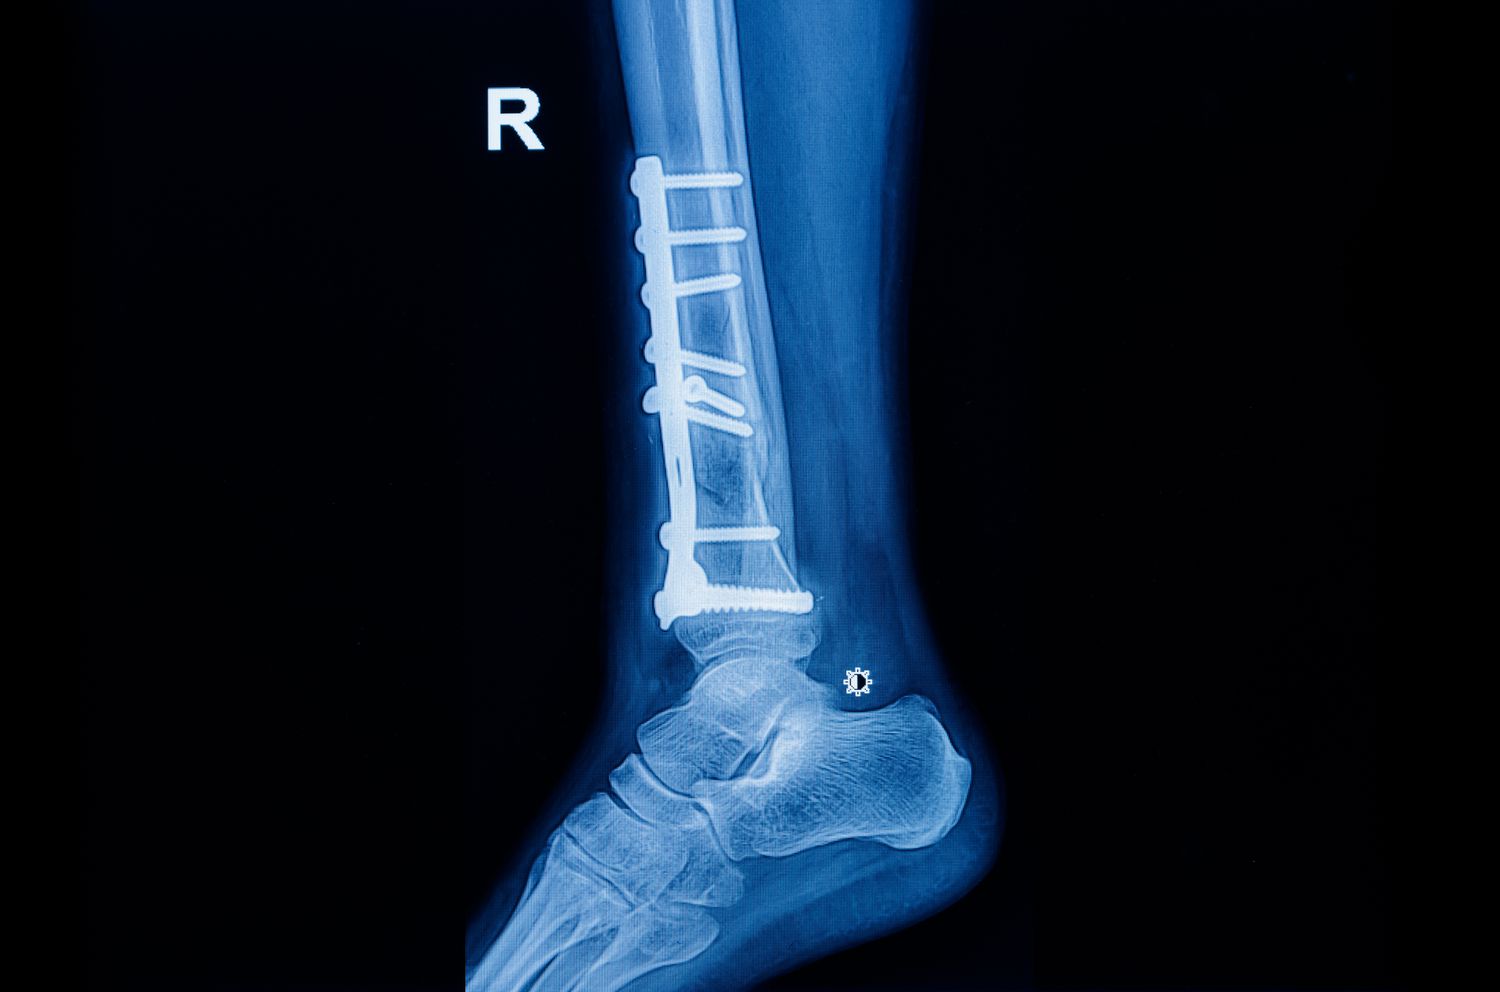

Sometimes, the X-ray looks worse than the outcome. A patient with a crushed lower leg discovered that the metal implant fixing his broken bones had bent months after surgery. He blamed the doctors for using substandard material and filed a complaint, but the court found the treatment had been textbook-perfect.

Over the next few months, the patient attended regular follow-ups. By December, the fracture site had aligned well and X-rays showed proper healing. But by the end of that month, one image revealed a slight bend in the implant. The patient claimed it was due to faulty fixation or poor-quality material, and alleged that the doctors suppressed the problem. He later underwent further care at another hospital, and approached the consumer forum demanding compensation for medical negligence.

The Kerala State Commission agreed. It observed that the failure occurred nearly five months after fixation, by which time the patient was already mobile. It accepted the expert’s opinion that such implant stress is possible in compound fractures and doesn’t imply defective equipment or poor surgery. The earlier order of negligence was set aside, and the doctors were cleared.

Not every hardware failure equals human error. In orthopaedics, implants can fail even when the treatment succeeds, especially in compound fractures where infection and delayed healing are common risks. Courts look for evidence of deviation from accepted practice — not merely an unfavourable X-ray.